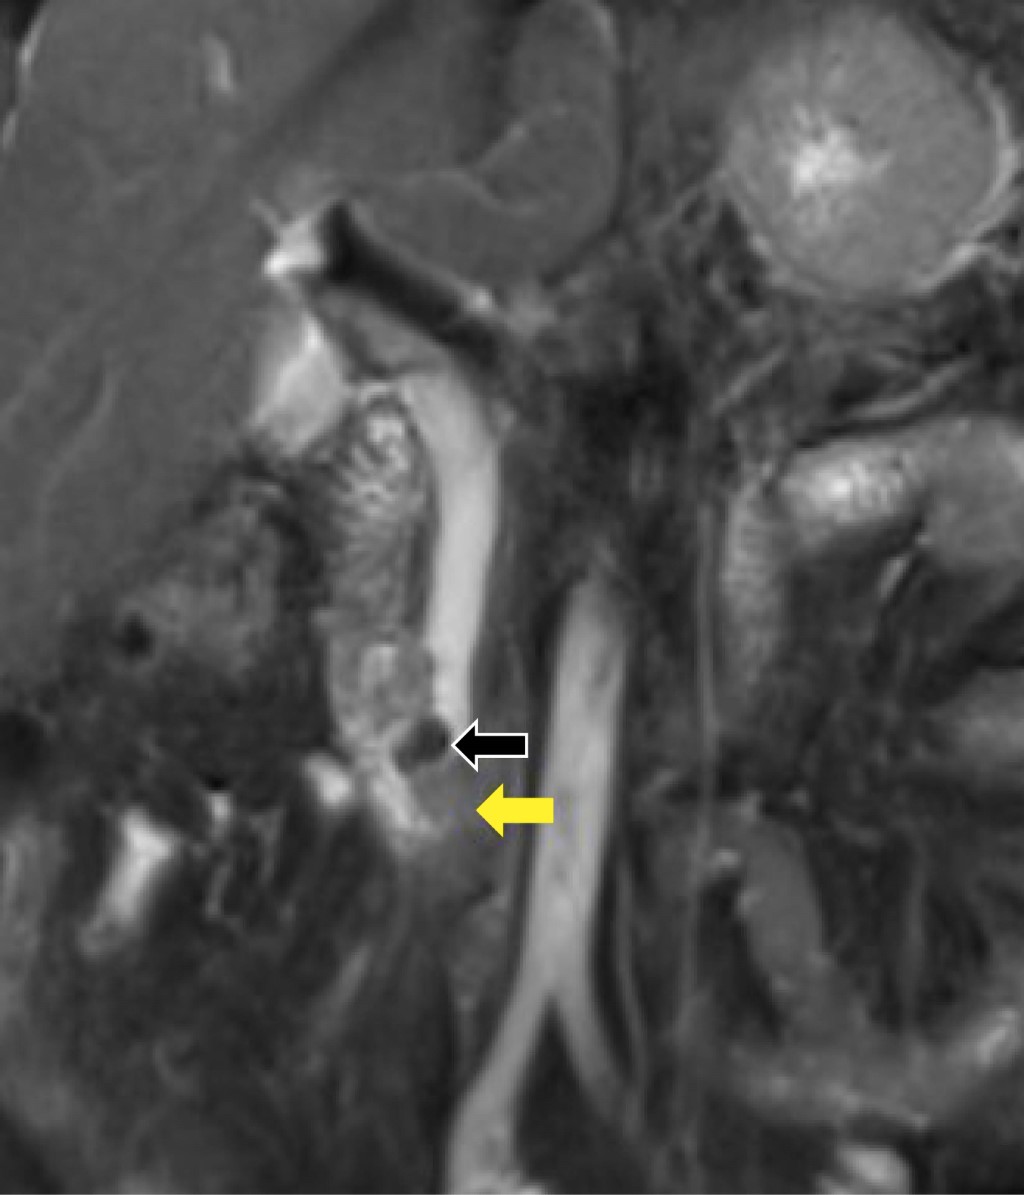

Primer caso clínico. Paciente femenino de 70 años con cuadros recurrentes de dolor abdominal, de 10 años de evolución, en epigastrio y sensación de plenitud gástrica, acompañada de emesis gastro-biliar, quien recibió tratamientos para dispepsia y cólico biliar que no fueron eficaces. Fue abordada previamente sin alteraciones por imagen y bioquímicos. Durante su abordaje diagnóstico sin ictericia, signo de Murphy y puntos pancreáticos negativos, con dolor abdominal epigástrico a la palpación profunda; paraclínicos con hiperbilirrubinemia a expensas de bilirrubina directa (BT 2.3 mg/dL, BD 1.60 mg/dL) y patrón colestásico (FA 220 U/L, GGT 316 U/L), sin leucocitosis (7.4×103/µL). Se realizó ultrasonido con datos indirectos de coledocolitiasis (colédoco de 16.5 mm), se solicitó colangiorresonancia magnética concluyente con coledocolitiasis y divertículo duodenal (Figura 1). Se efectuó intervención quirúrgica con colangiografía y CPRE transoperatoria, con extracción de lito impactado en papila duodenal, así como realización de esfinterotomía, encontrando divertículo duodenal a 2.5 cm de la papila de Vater (Figura 2), sin complicaciones, con mejoría evidente de dolor abdominal, por paraclínicos sin anormalidades. Se logró el egreso de la paciente y al seguimiento consecutivo no hubo anormalidades.

El diagnóstico de DDY comúnmente es incidental; sin embargo, no debe olvidarse, y debe tomarse como diagnóstico diferencial como causa de dolor abdominal intermitente. Las pruebas de imagen como tomografía y resonancia magnética son esenciales, mismas que muestran una cavidad de pared delgada en la segunda porción del duodeno (Figura 1), confundida a menudo con absceso pancreático o neoplasia quística de la cabeza del páncreas. El ultrasonido endoscópico es útil para descartar neoplasias; no obstante, la CPRE continúa siendo el estándar de oro diagnóstico-terapéutico, con tasas superiores de éxito de 95% y recurrencia de 10-24%.1,5,12

Figura 1